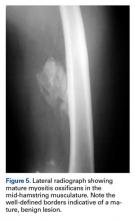

Similar to other muscle strains, hamstring strains are a clinical diagnosis and generally do not necessitate advanced imaging studies except to assess the degree of damage (ie, partial vs complete rupture) and to rule out other injuries, especially if the athlete fails to respond to treatment. Plain radiographs in acute cases are usually unremarkable. However, more severe injuries may go on to develop myositis ossificans similar to quadriceps soft tissue injuries (Figure 5).